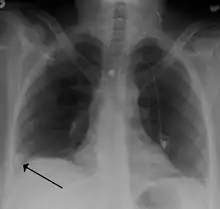

Large saddle embolus seen in the pulmonary artery (white arrows).